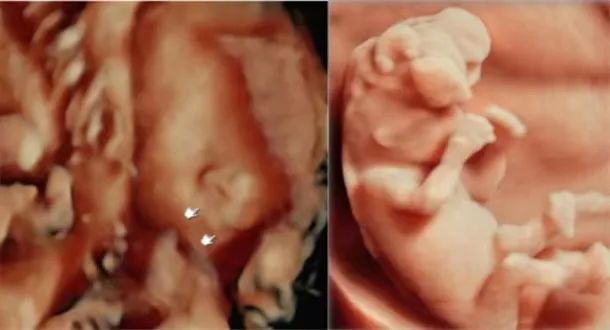

胎儿排畸检查 内外一览无余

能够通过将更多、更细致的切面图像进行离线保存来观察胎儿唇、腭部位的发育状况,帮助医生诊断唇腭裂。“煊光”平台灵活的三维四维技术,可用于胎儿颜面部、中枢系统及脊柱异常的显示,通过细致的多切面成像分析胎儿的解剖结构及发育状况。

“煊影成像”技术可以清晰显示胎儿的内部结构,增加组织透明度调节,实现100级可调,从内到外,一览无余。在早孕、双胎等评估方面极具优势。